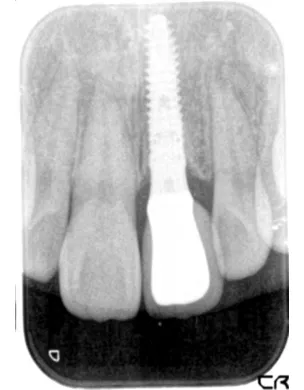

治療完了時

| 患者様のお悩み | 外傷で歯が抜けた |

|---|---|

| 治療法・使用素材 | インプラント治療の後、セラミック治療 |

| 患者様の年代 | 20代 |

| 治療開始年齢 | 20代 |

| 治療にかかった期間 | 8か月 |

| 性別 | 女性 |

| この治療のリスクについて | インプラントが正しい位置に入るかどうか |

| 治療にかかった費用 | 45万円 |